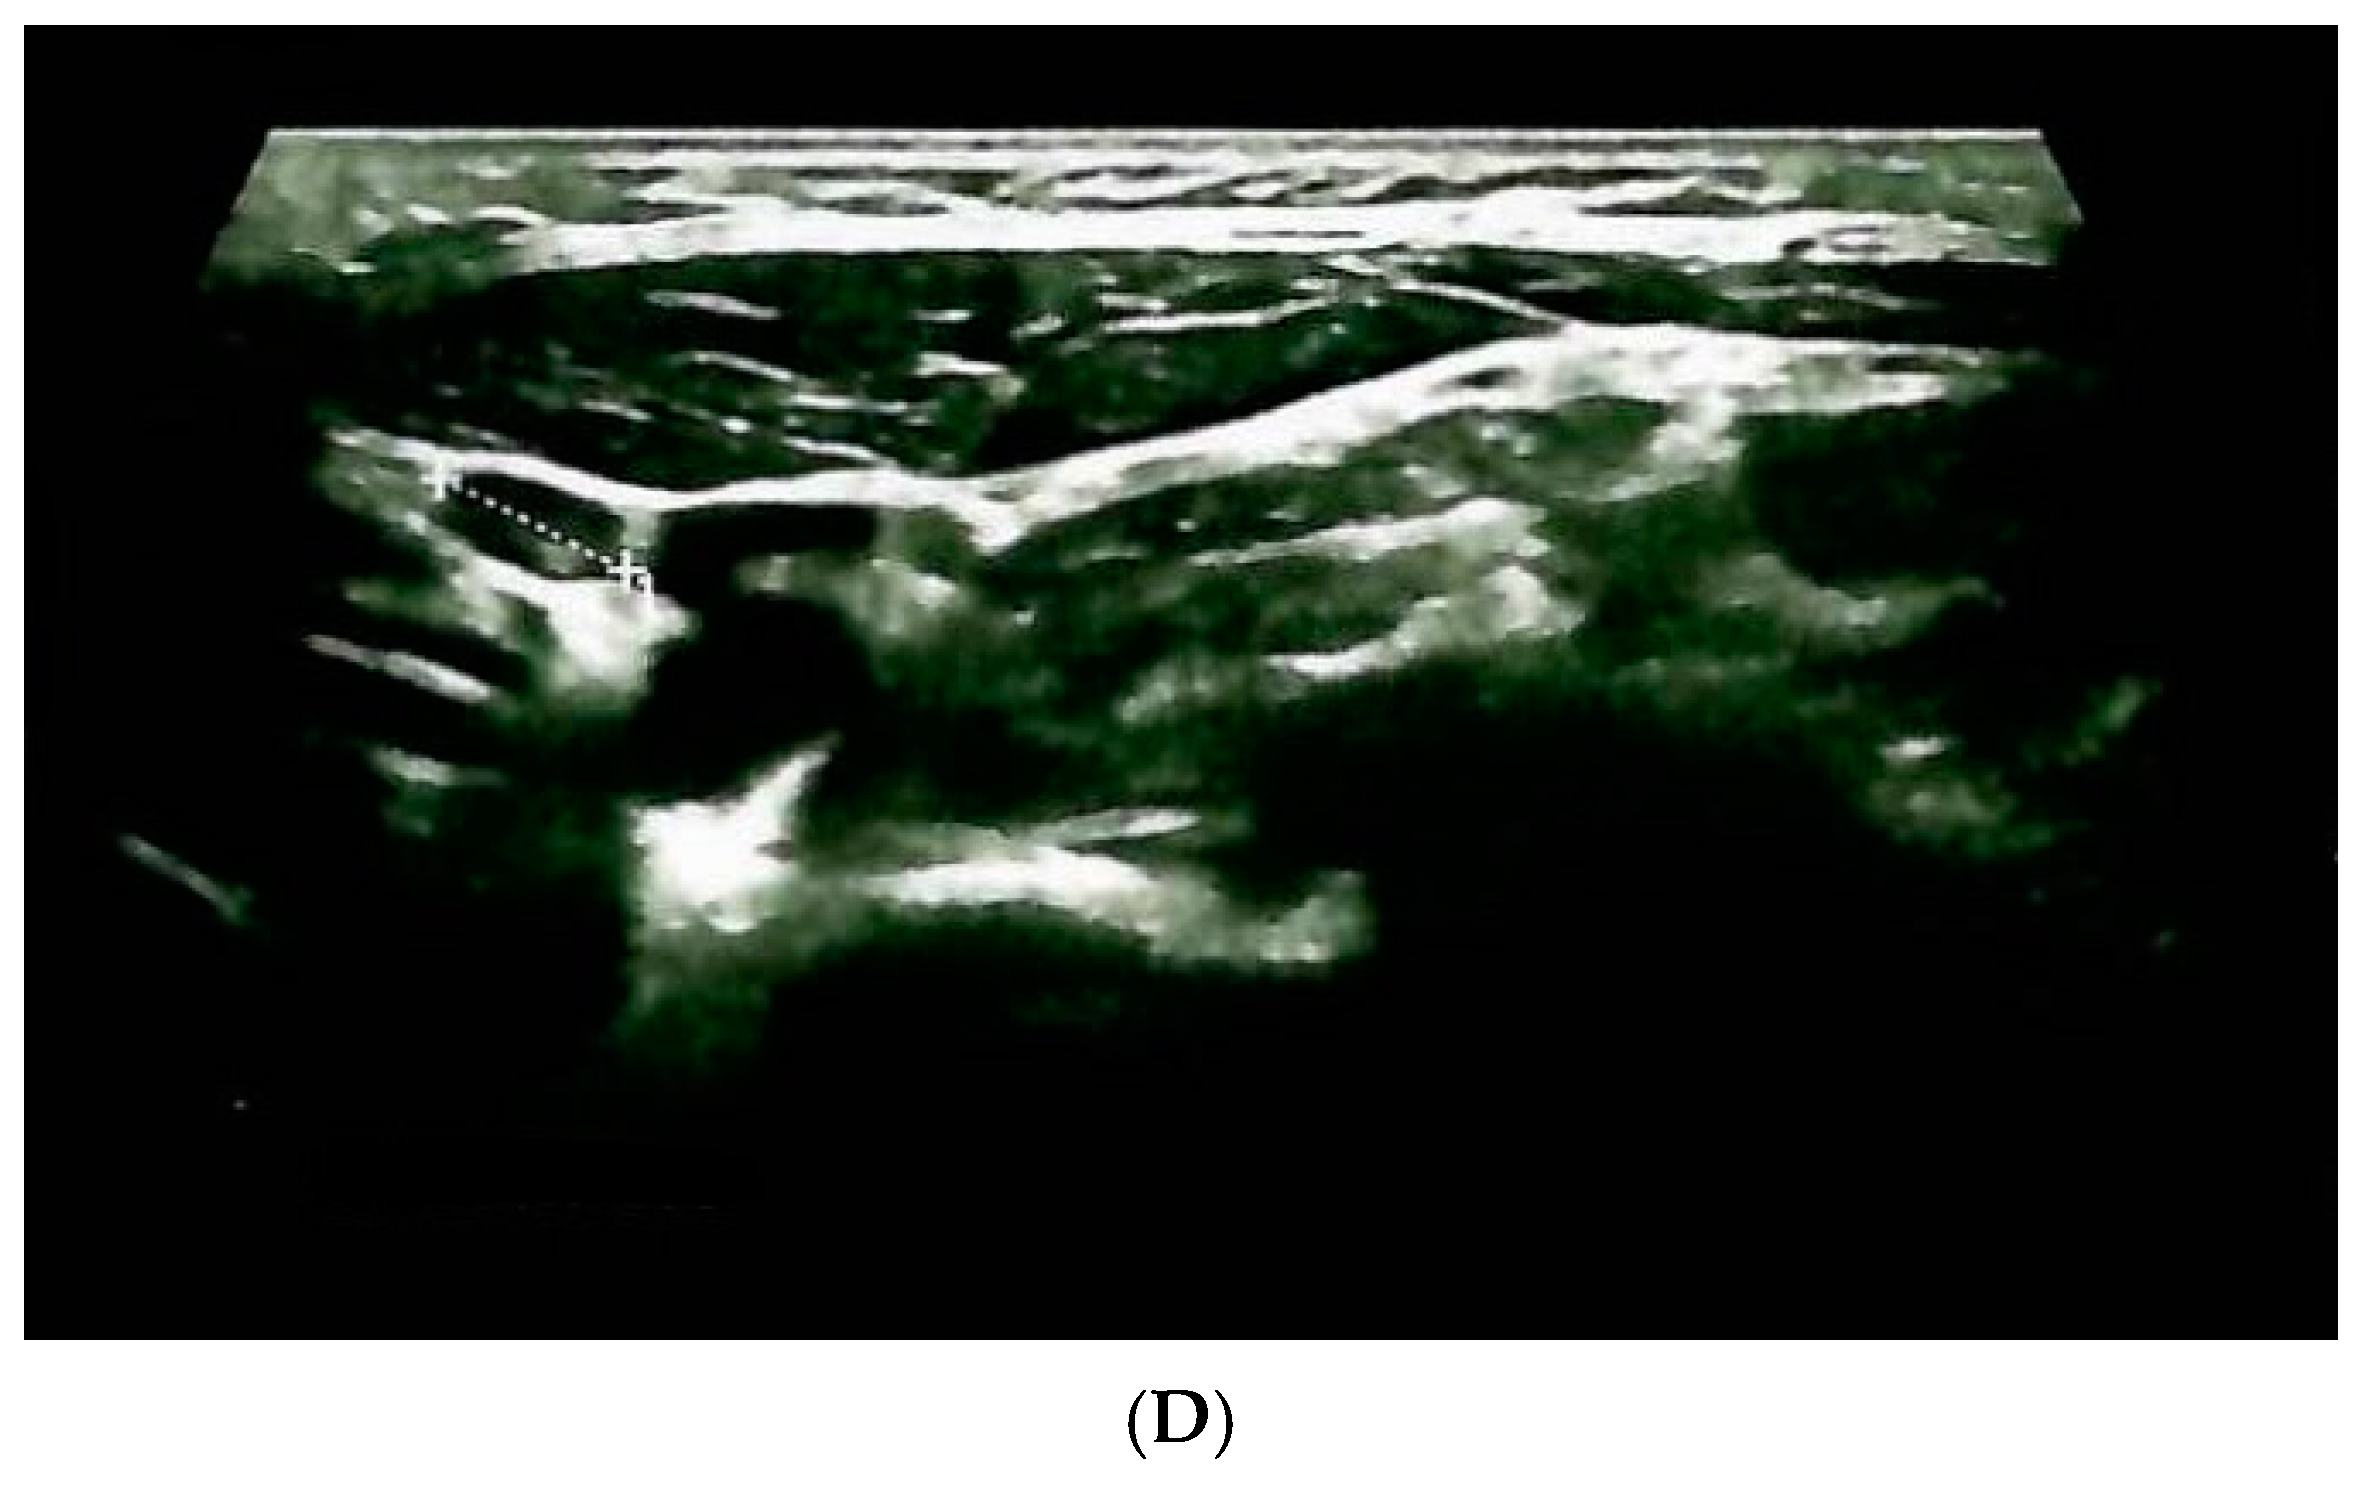

| Confirmation of the endocrine tumor/cancer | Yes (+2/10 cervical lymph nodes invasion) | Yes (bilateral) | Yes (left inferior parathyroid tumor) |

| Age at diagnosis | 31 years (+ RET testing at 31 years) | ||

| Hormonal assays before surgery | Calcitonin = 304 ng/mL (normal: 1–4.8) | Plasma metanephrines = 300 pg/mL (normal: 0–90) Plasma normetanephrines = 400 pg/mL (normal: 20–200) | PTH = 122 pg/mL (normal: 15–65) Total serum calcium = 11.4 mg/dL |

| Surgery | Yes (synchronous total thyroidectomy, neck lymph nodes dissection and selective removal of a single parathyroid tumor) | Yes (synchronous bilateral adrenalectomy) | Yes |

| Age at the moment of surgery | 31 years | ||

| Current post-operatory status | |||

| Primary hypothyroidism | Chronic primary adrenal insufficiency | Hypoparathyroidism | |

| Latest hormonal assessment | TSH = 5.96 μIU/mL * (normal: 0.35–4.94) FT4 = 11.69 pmol/L * (normal: 9–19) * under levothyroxine 100 μg/day Calcitonin = 1.85 ng/mL (normal: 1–4.8) | Plasma metanephrines = 31 pg/mL (normal: 0–90) Plasma normetanephrines = 155 pg/mL (normal: 20–200) ACTH = 21.8 pg/mL ** (normal: 3–66) ** Under hydrocortisone 25 mg/day + fludrocortisone 0.1 mg/day | PTH = 10.76 pg/mL*** (normal: 15–65) Total serum calcium = 6.54 mg/dL *** (normal: 8.4–10.2) *** Under calcitriol 0.5 μg per day + 500–1000 mg oral calcium/day |